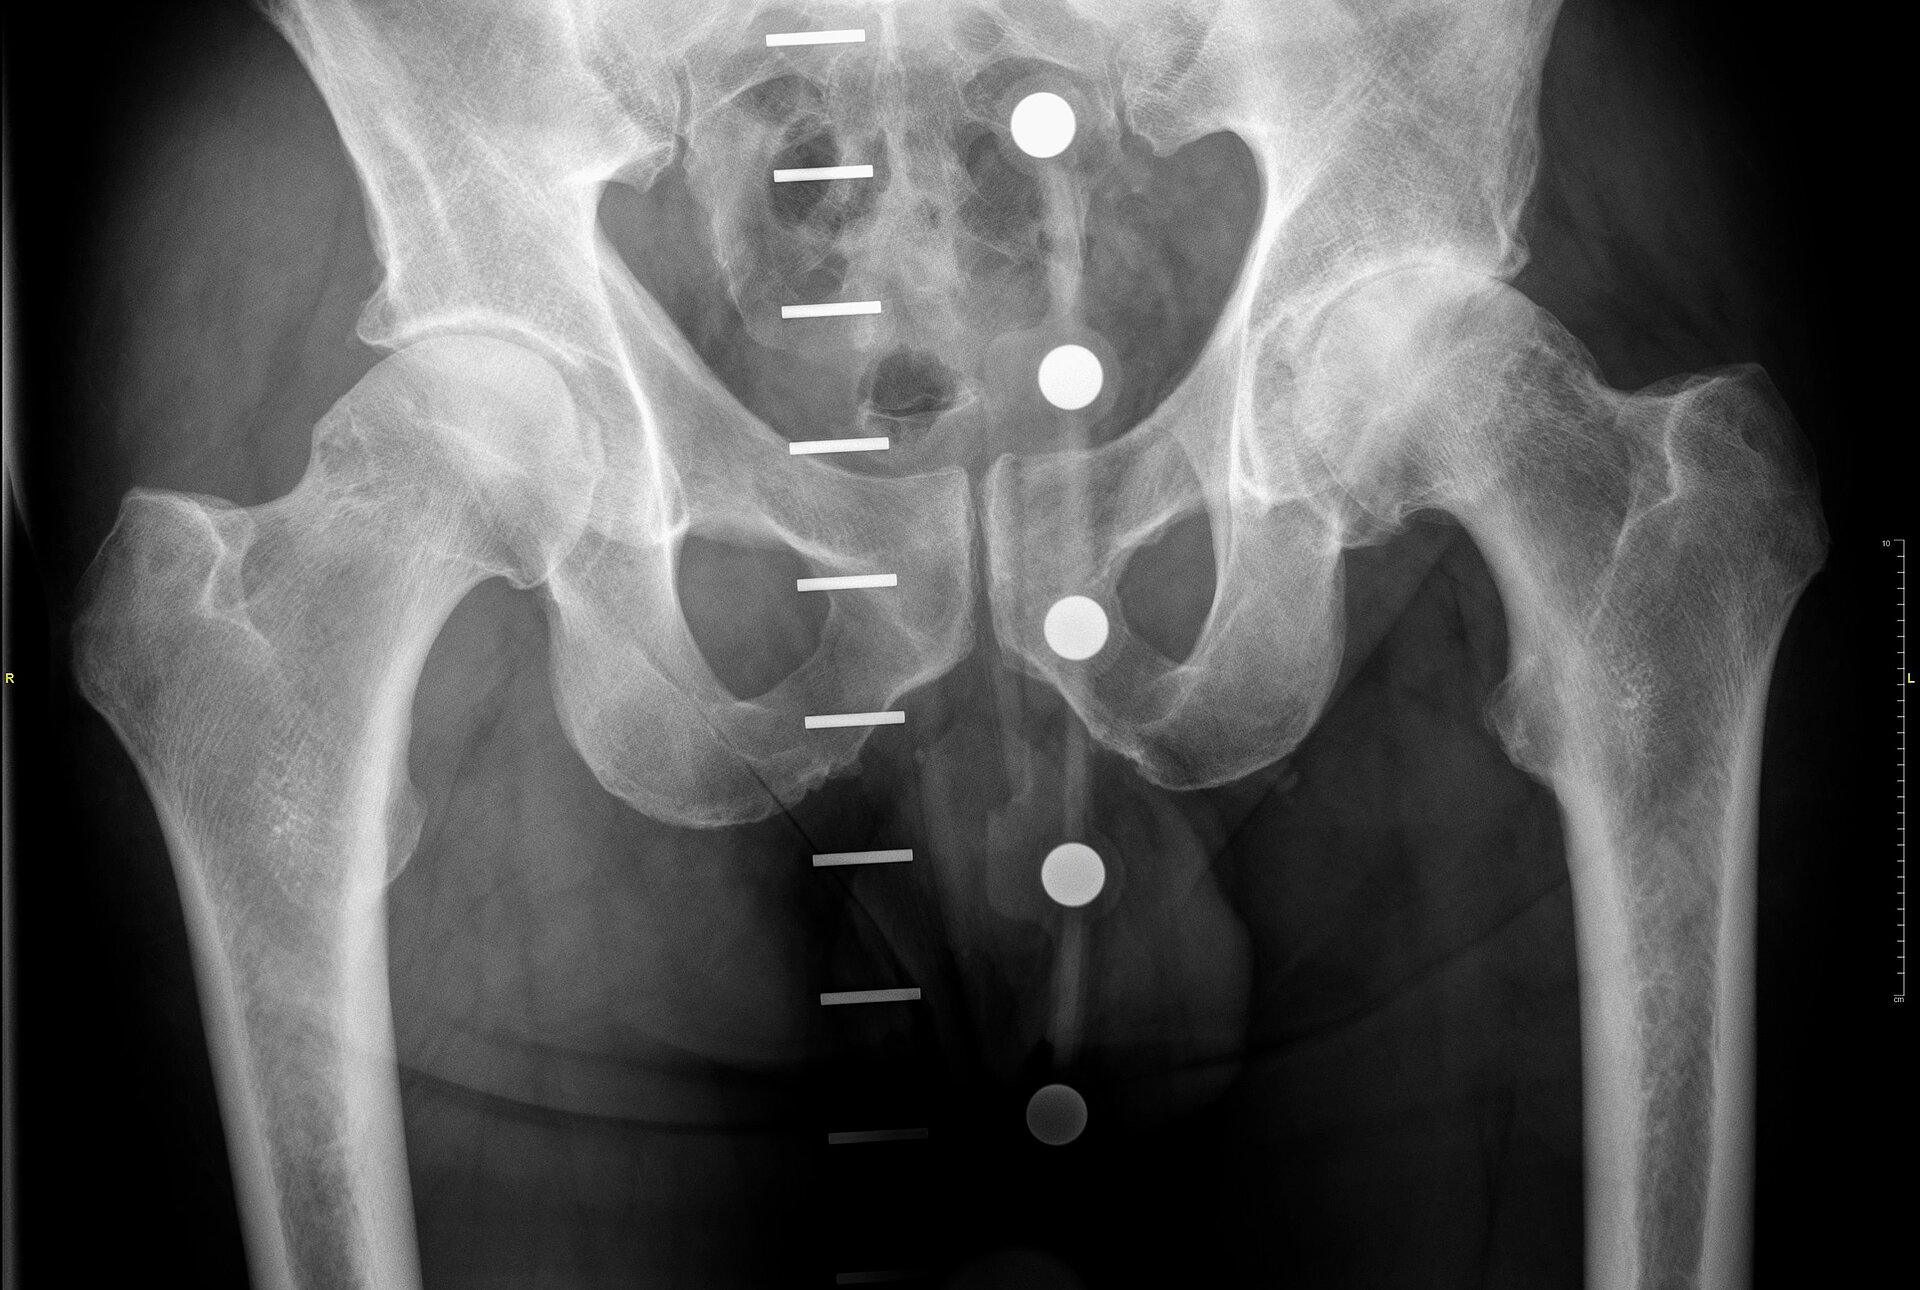

A 60 year old recently-retired consultant anaesthetist was seen with significant pain and restricted mobility associated with his arthritic left hip. His situation had progressed rapidly and by the time of his surgery he was experiencing significant discomfort with walking and had groin and proximal thigh pain at night and at rest after activity. Clinical examination revealed a fit and healthy male with a fixed flexion deformity in his left hip and a painful restriction in his available range of movement. Radiology confirmed significant degenerative wear in the hip with no cystic change or sinister concern. The patient was an extremely keen and active gentleman who amongst other activities, such as walking, yoga, training and cycling, was also a highly accomplished climber. He was very keen to return to all his recreational activities following surgery. In addition, he had a previously diagnosed metal sensitivity and reaction and was not happy to be considered for a metal-on-metal bearing for that reason.